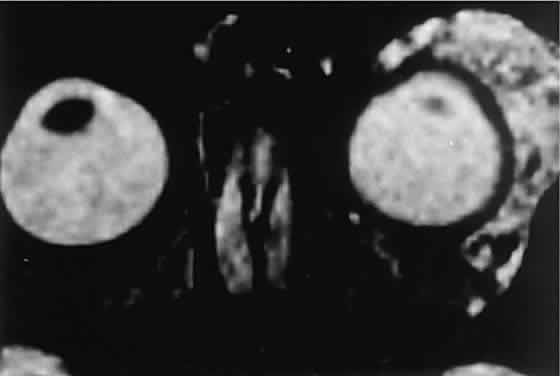

Fig. 2. MRI shows an intraconal tumor of lower intensity than the medial rectus

muscle. The proximal muscle is splayed rather than compressed, suggesting

that the lesion originated within the medial rectus. The diagnosis

was alveolar rhabdomyosarcoma. Fig. 2. MRI shows an intraconal tumor of lower intensity than the medial rectus

muscle. The proximal muscle is splayed rather than compressed, suggesting

that the lesion originated within the medial rectus. The diagnosis

was alveolar rhabdomyosarcoma.